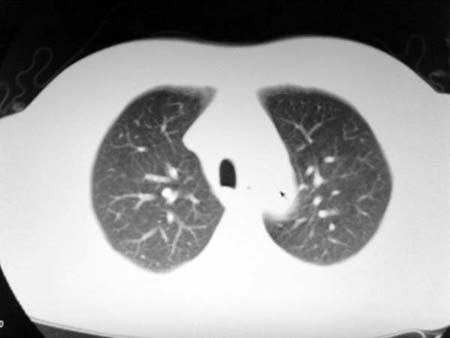

以下是引用qian在2008-4-27 17:02:00的发言:[br]考虑右下肺肺段隔离症伴有感染,建议做增强看看。

以下是引用zsl6918在2008-4-27 17:13:00的发言:[br]考虑右肺下叶炎性病变可能性大,建议抗炎治疗后复查,现有资料不能完全除外肺癌可能。